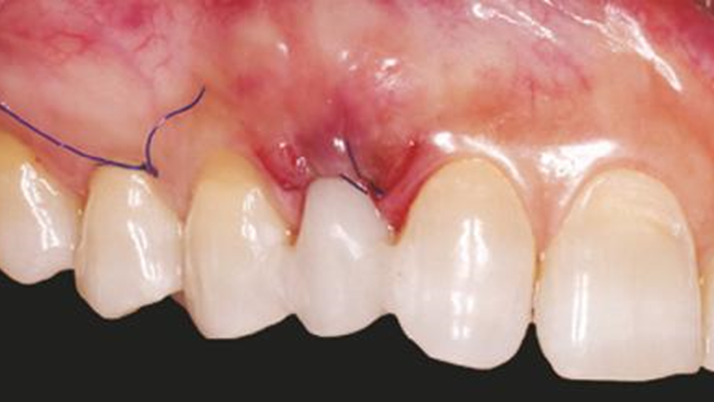

Clinical case: Immediate placement in maxillary anterior narrow space using Advanced Intermezzo

- Courtesy of Dr. Jung Sam Lee, Korea -

Advanced Intermezzo. anterior esthetics, esthetic, provisional restoration, esthetic zone, #13, maxillary anterior, Dr. Jung Sam Lee, anterior aesthetics, aesthetic, aesthetics

Advanced Intermezzo implant system